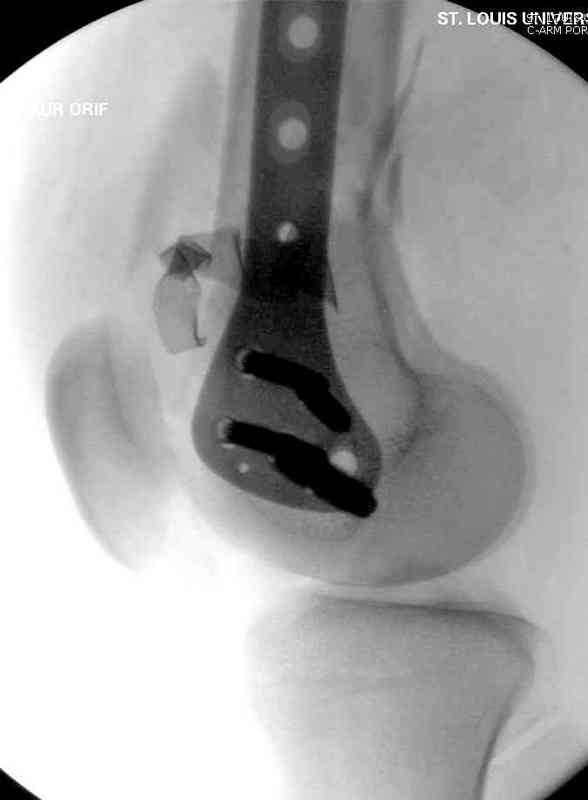

Пострадавшему 23, пистолетная огнестрельная не кроветочащая рана, меньше одного см диаметром, входное отверстие расположено латерально, и выход передне-медиально, и еще имеется второе пулевое ранение правой navicular bone с этой стороны.

Доступ был латеральный, при вскрытии с задней

поверхности бедра обнаружили кровотечение. Поднятием давления на заранее установленном турникете на конечности проконтролировали кровотечение.

В данном случае мы не ставили осуществление гемостаза приоритетным, после 30 минут больной оставлен вызванному сосудистому хирургу со стабильной фиксацией бедра. Несмотря на выбранный передне-медиальный доступ, хирург произвел восстановление сосудистого повреждения.

При близости сосудов к многооскольчатому повреждению костей, сперва необходимо удостовериться в наличии повреждения сосудов без применения турникета.

Латерально пластину защитили ушиванием

илио-тибиального тракта, а медиальная сторона была ушита мышцей, и все раны закрыли ваккумированием (VAC)